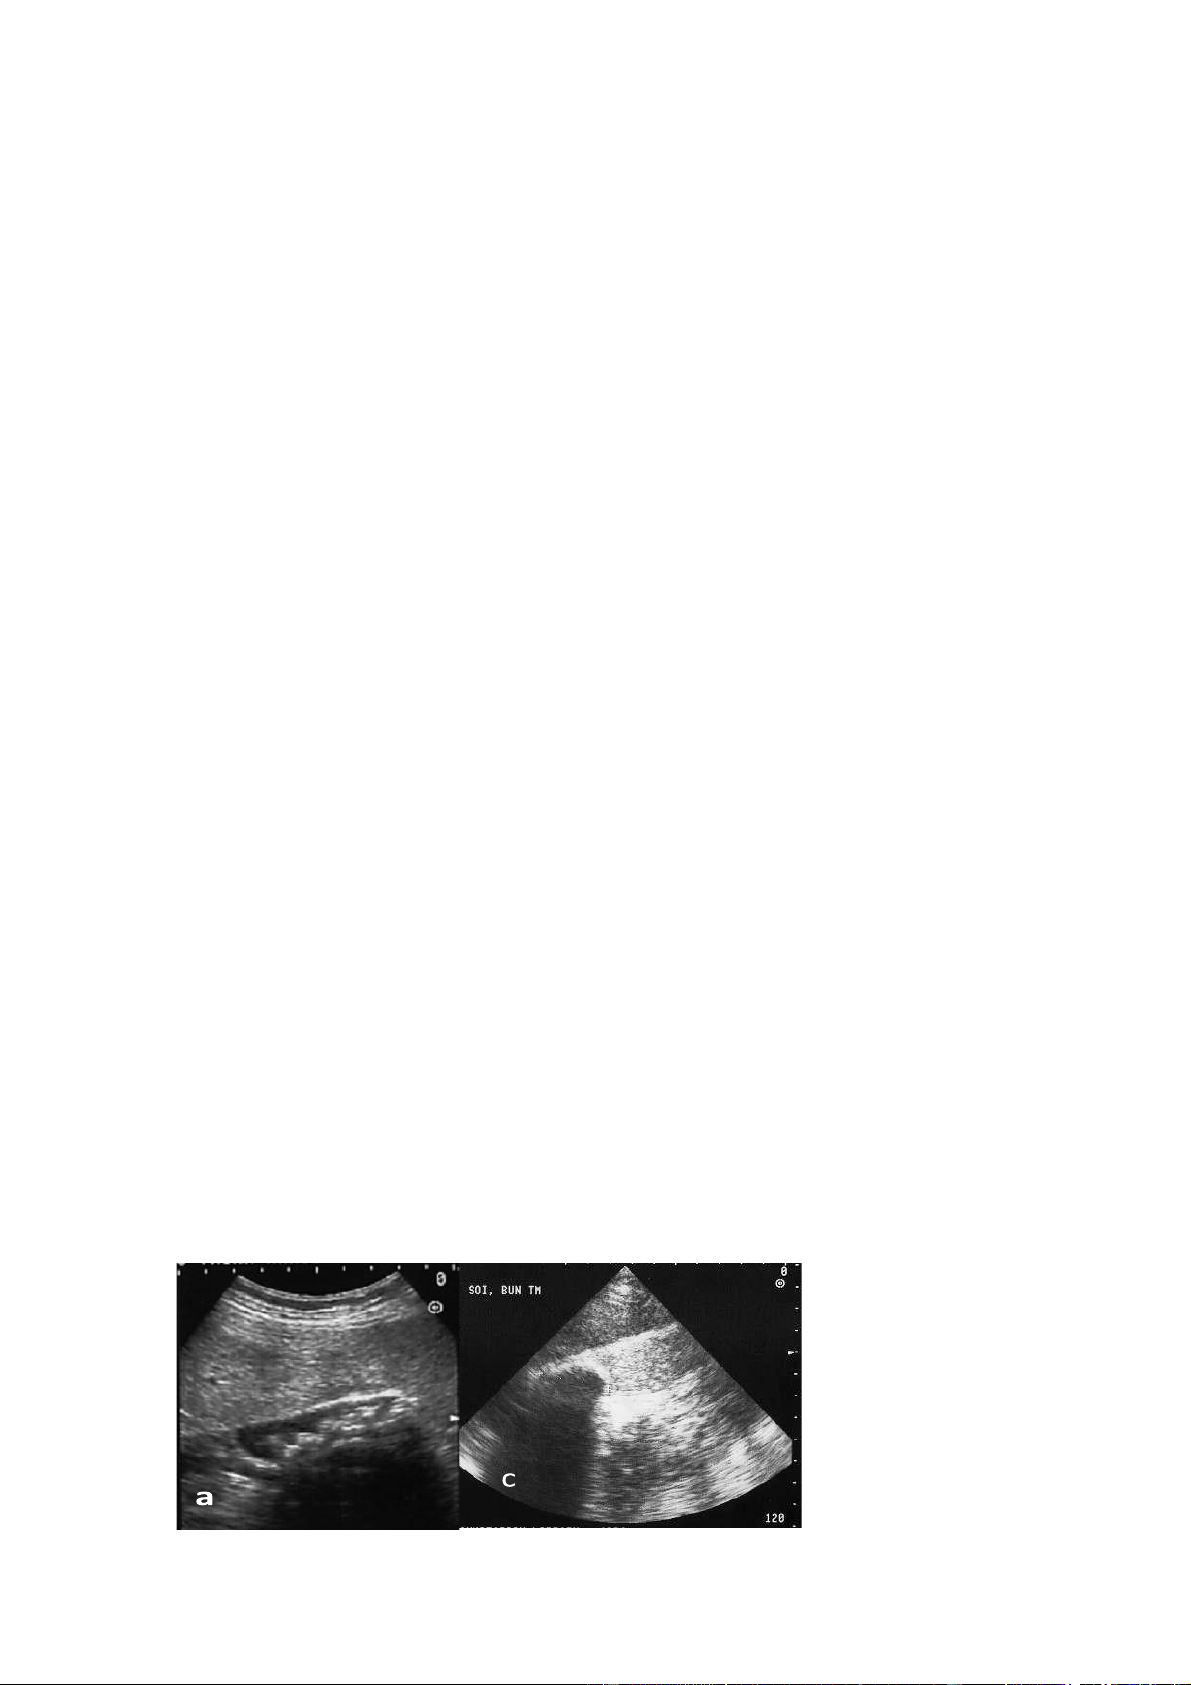

Hinh 5.1. Hình ảnh siêua âm xơ gan:

a. Bờ gan mấp mô () và nhu mô gan

không đều, b. Cách đo để đáng giá tỷ lệ

phân thuỳ I trên gan trái: Nhánh trái

tĩnh mạch cửa (V) tĩnh mạch chủ

( TMC), c. Gan phải teo nhỏ, dịch cổ

chướng và bờ gan mấp mô lOMoAR cPSD| 58490434 5.2. Gan nhiễm mỡ